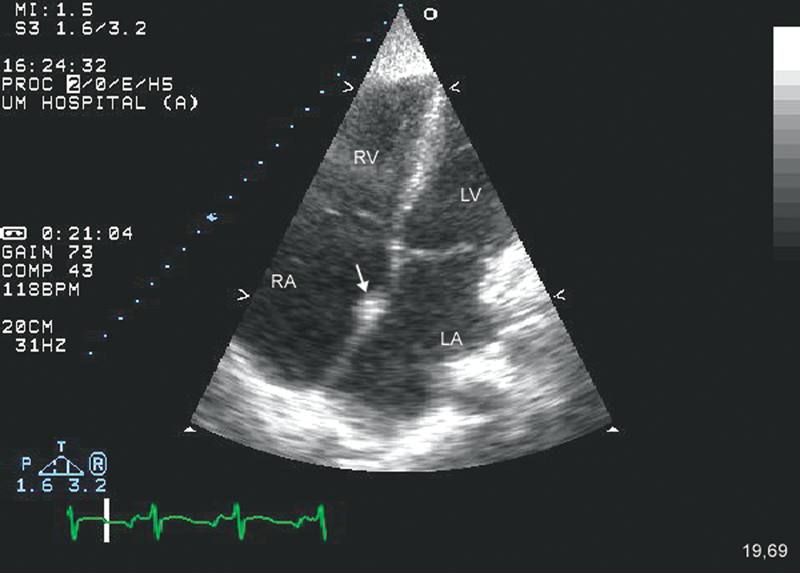

فحوصات تشخيصية لبعض امراض القلب والشرايين التاجية